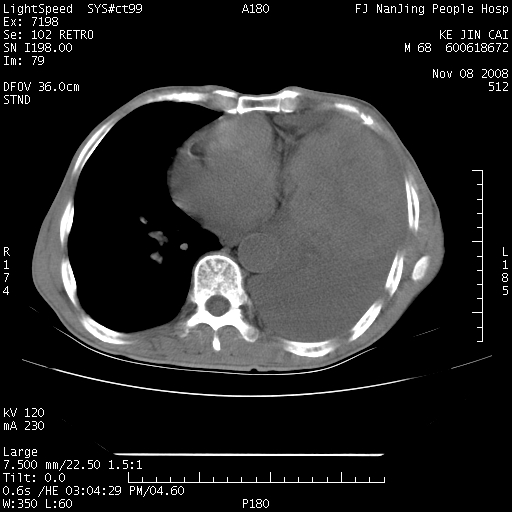

是个很有看头的病例,咋人气那么不旺?没多少人兴趣呢?这个病例几大怪:1   恶性肿瘤侵犯心肌左房怪,心肌一般不会被恶性肿瘤侵犯吧?2   左下肺均匀实变怪,内无含气,有别一般不张实变,含气肺泡完全为液体取代,而非一般不张实变的肺萎陷,冷不丁还以为是肿大的脾脏3   肿瘤本身怪,像tb肺不张4   这么有看头的病例没人气怪。呵呵。

左肺恶性肿瘤侵犯肺动脉,左心房内瘤栓,胸膜转移。